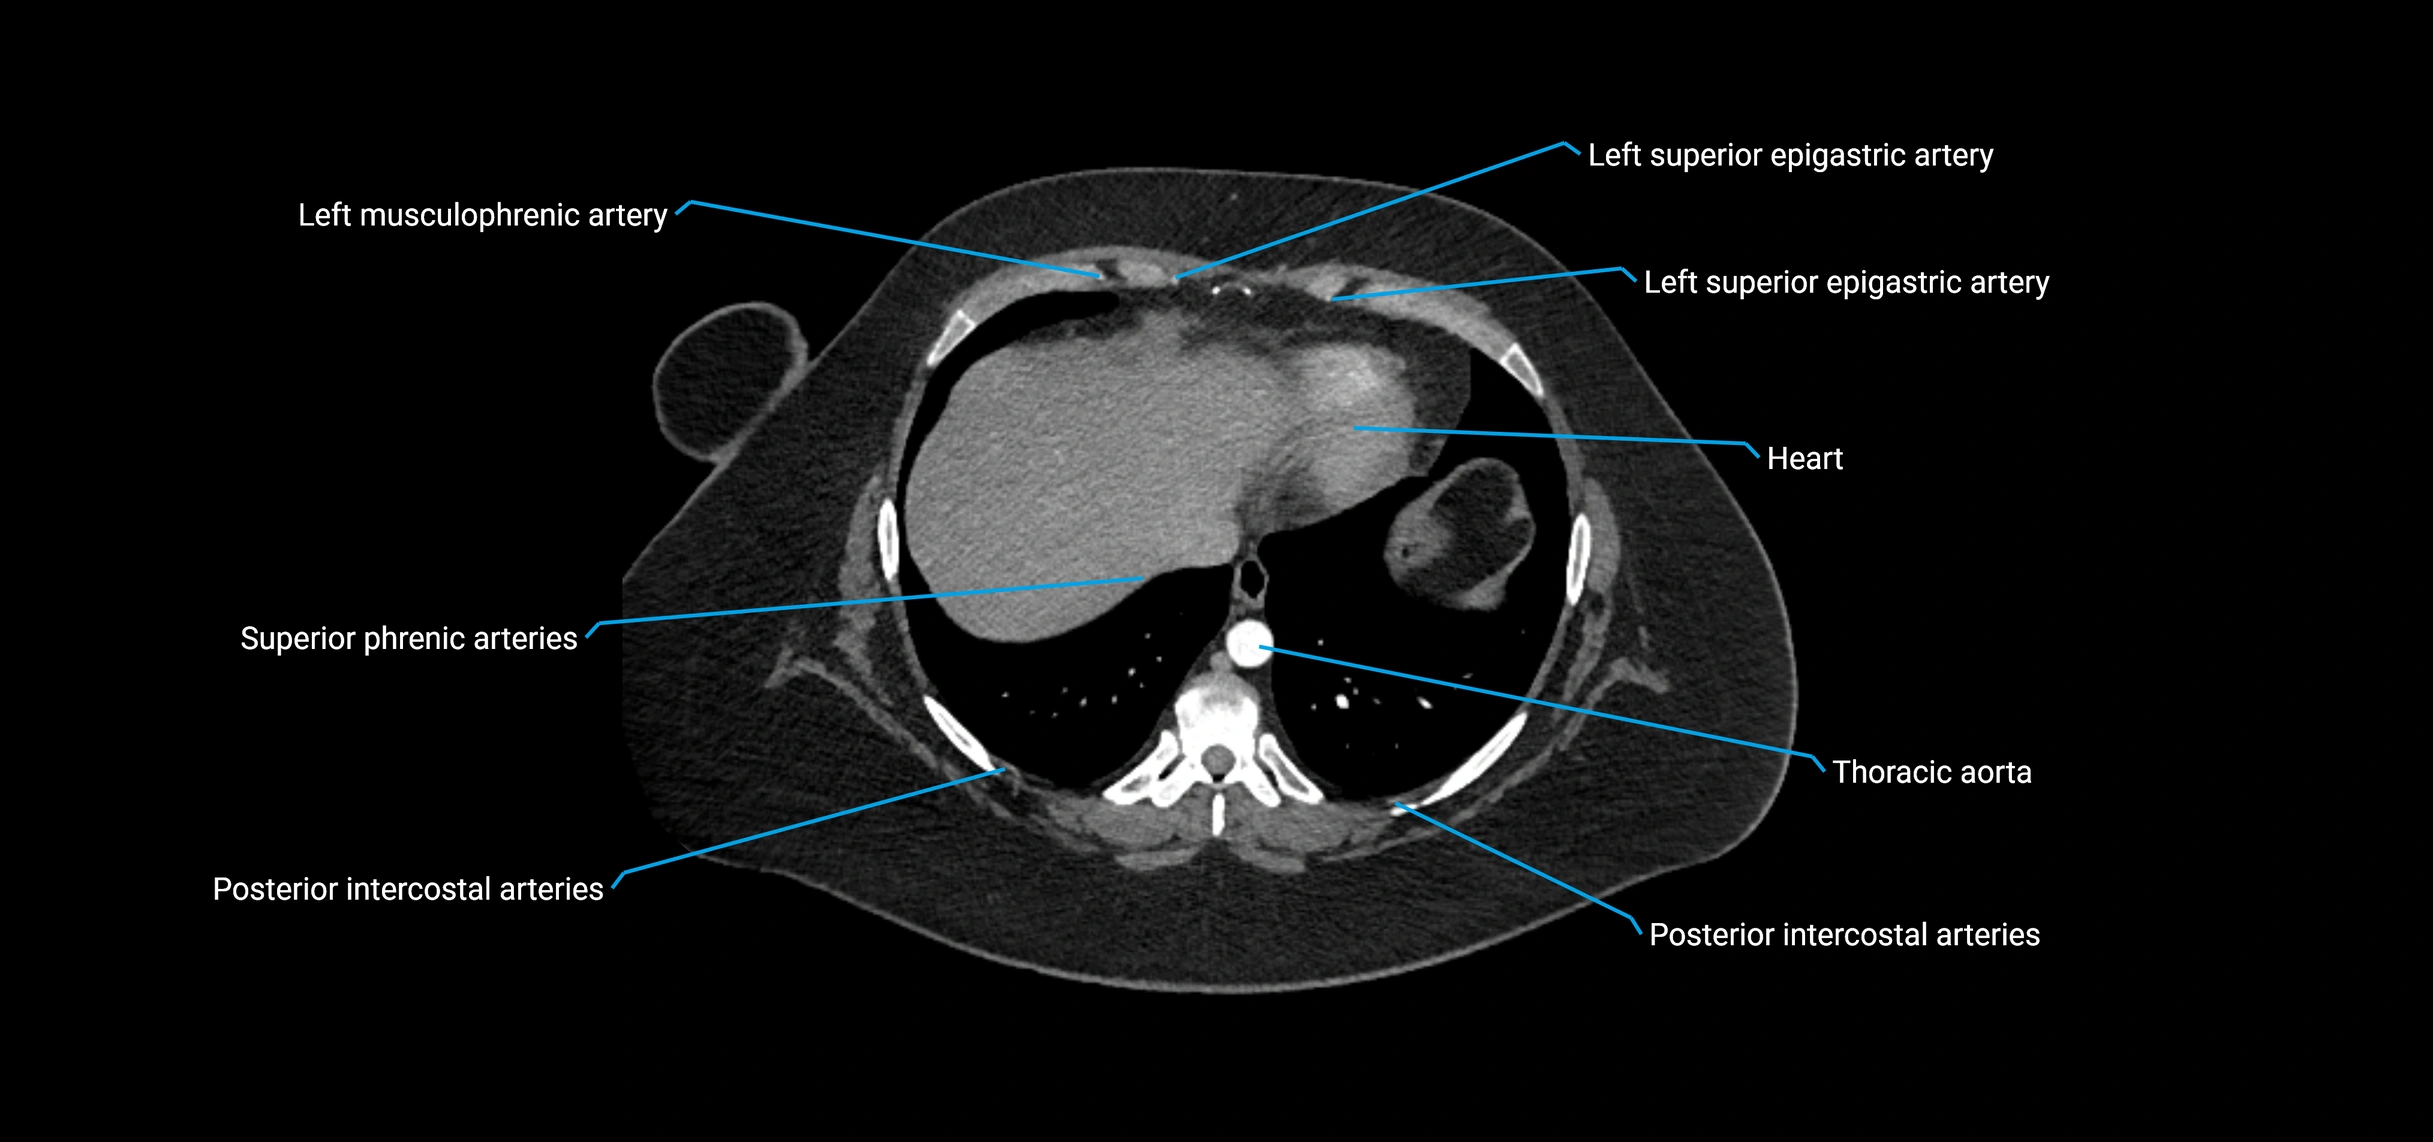

MRI images

image

MRI Appearance

T1-weighted images:

• Flowing blood appears as a signal void (black lumen)

• Vessel wall appears as a thin hypointense rim; retroperitoneal fat enhances contrast

T2-weighted images:

• Lumen remains a signal void due to flow

T1 Post-Contrast (Gadolinium-enhanced):

• Aortic lumen enhances brightly and homogeneously

• Clearly demonstrates aneurysm, stenosis, dissection, mural thrombus, or aortic wall enhancement in vasculitis